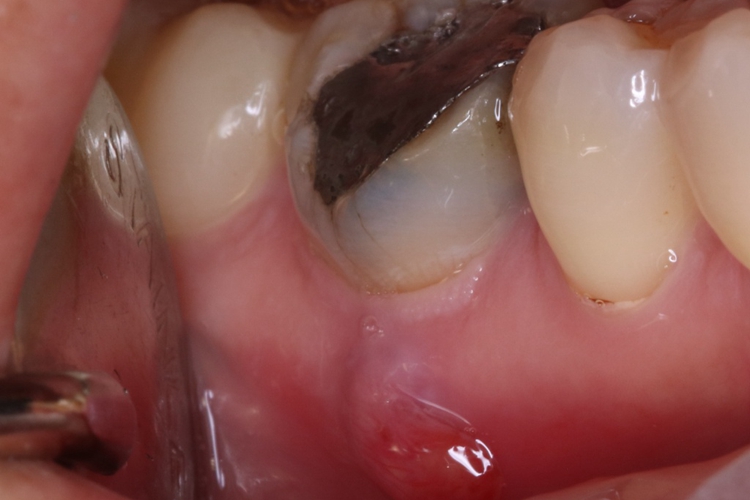

根尖囊肿生长缓慢,病人多无自觉症状。其损害可发生在牙齿,口腔检查可见患牙有龋损或其他非龋性牙体病,或牙冠变色失去光泽。叩诊可有不适感,温度测验患牙无反应。

根尖囊肿可由慢性根尖周肉芽肿或慢性根尖周脓肿等发展而来。因牙根感染、牙髓坏死,进而根尖周形成肉芽肿或脓肿,随后上皮细胞长入其内作为衬里形成囊肿内膜,病牙根尖突入囊肿腔内。增生的上皮团中央发生变性与液化,周围组织液不断渗出,逐渐形成根尖囊肿。

根尖囊肿需遵医嘱通过取上颌窦根治术式切除囊肿。若病牙尚稳固,有保留可能,则行根尖切除或根管治疗以避免囊肿再发。否则,应同时拔除病牙。